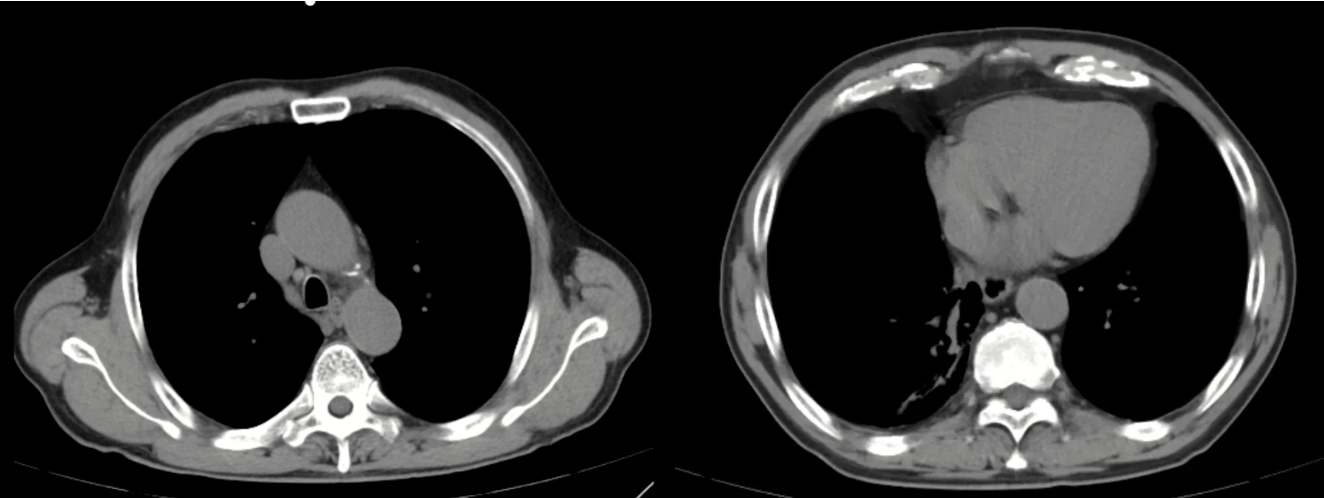

我院首次与患者病情交锋是在2025年6月,患者入院后,我们为其复查了胸部CT。影像学报告依旧冷峻:右肺下叶占位,考虑恶性肿瘤可能大,伴远端阻塞性肺炎、癌性淋巴管炎可能;纵隔及右肺门多发淋巴结肿大。当时看来,肿瘤的影像学特征似乎十分典型。

图1:外院肺部CT

然而,实验室检查却给我们的判断投下了一道“阴影”:血清免疫球蛋白G4(IgG4)高达3.86 g/L(正常参考范围:0.03-2.01 g/L)。这是一个明确的升高信号。尽管肿瘤性疾病也可能伴随非特异性的免疫球蛋白变化,但如此显著的IgG4升高,我们不得不拓宽鉴别诊断的思路。